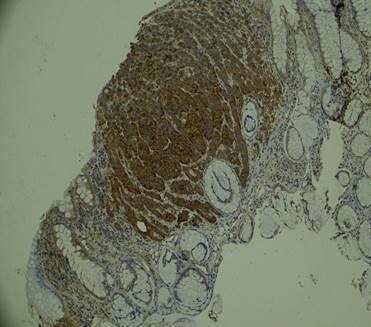

La biopsia reportó un tumor neuroendocrino bien diferenciado G2 con infiltración del corion y el margen de resección comprometido. La técnica de inmunohistoquímica fue positiva para cromogranina, sinaptofisina y Ki 67: 10% (Fig. 1).

Figura 1. Mucosa colónica con una proliferación neoplásica de células con núcleos redondeados hipercromáticos, en sal y pimienta que se disponen en rosetas.